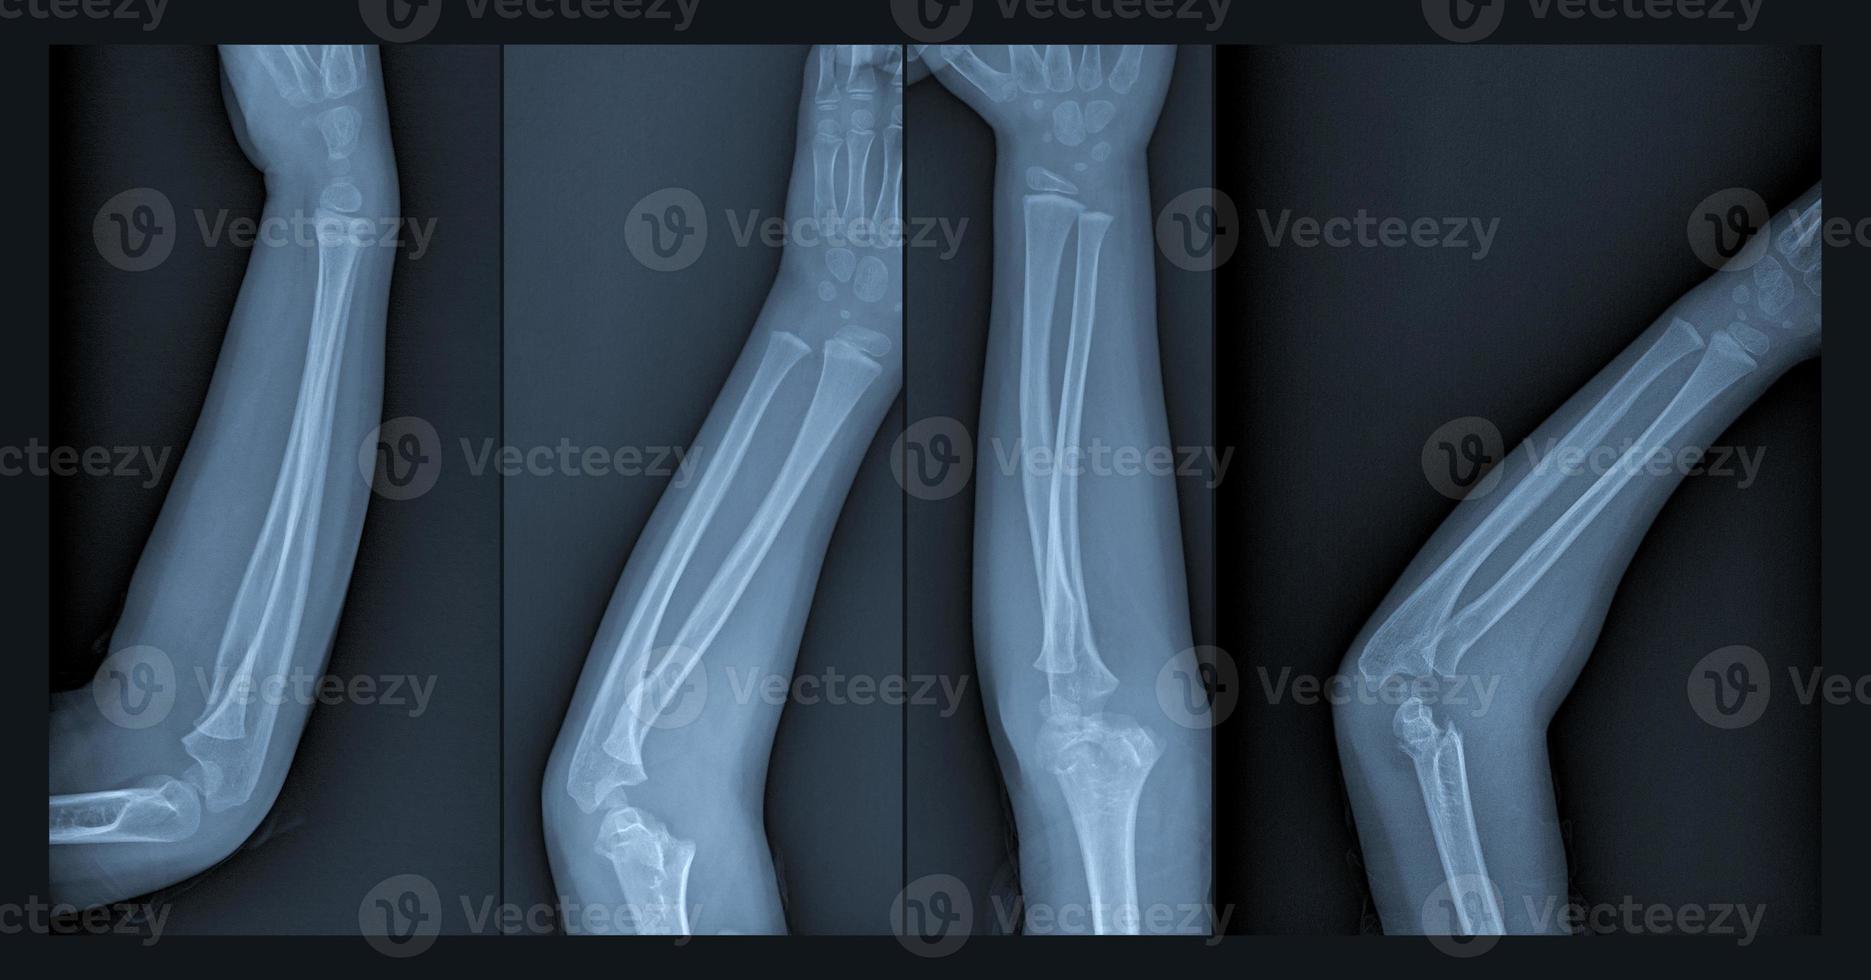

From www.vecteezy.com

Broken arm xray 6888485 Stock Photo at Vecteezy A Broken Arm X-Ray With a broken arm, one or more bones are cracked. It’s more common to break one of the two bones in. The doctor may examine your shoulder, upper arm, elbow, wrist, and hand, even if you complain only of arm pain. You may have broken your arm or wrist if you've injured it and it suddenly became: If bones poke. A Broken Arm X-Ray.

Broken arm xray 6518683 Stock Photo at Vecteezy A Broken Arm X-Ray They can also show how many pieces of broken bone there are. At least 2 views of the arm are taken. With a broken arm, one or more bones are cracked. They might place a splint or cast to keep your arm still and in a better position. Learn about types, treatments, symptoms, healing time, pain relief, and surgery. A. A Broken Arm X-Ray.